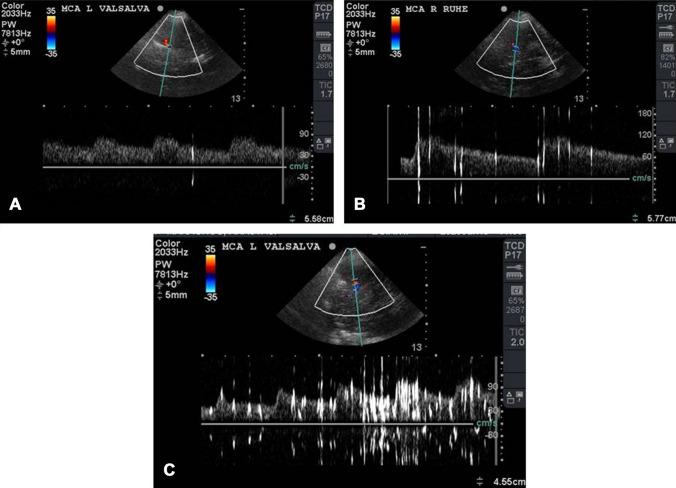

Sickle cell disease (SCD) is an inherited monogenic hemoglobinopathy characterized by formation of sickle erythrocytes under conditions of deoxygenation. Sickle erythrocytes can lead to thrombus formation and vaso-occlusive episodes that may result in hemolytic anemia, pain crisis and multiple organ damage. Moreover, SCD is characterized by endothelial damage, increased inflammatory response, platelet activation and aggravation, and activation of both the intrinsic and the extrinsic coagulation pathways. Cerebrovascular events constitute an important clinical complication of SCD. Children with SCD have a 300-fold higher risk of acute stroke and by the age of 45 about 25% of patients have suffered an overt stoke. Management and prevention of stroke in patients with SCD is not well defined. Moreover, the presence of patent foramen ovale (PFO) increases the risk of the occurrence of an embolic cerebrovascular event. The role of PFO closure and antiplatelet or anticoagulation therapy has not been well investigated. Moreover, during COVID-19 pandemic and taking into account the increased rates of thrombotic events and the difficulties in blood transfusion, management of SCD patients is even more challenging and difficult, since data are scarce regarding stroke occurrence and management in this specific population in the COVID-19 era. This review focuses on pathophysiology of stroke in patients with SCD and possible treatment strategies in the presence of PFO.

镰状细胞病(SCD)是一种遗传性单基因血红蛋白病,其特征是在缺氧条件下形成镰状红细胞。镰状红细胞可导致血栓形成和血管阻塞发作,从而导致溶血性贫血、疼痛危象和多器官损伤。此外,SCD 的特征还包括内皮损伤、炎症反应增加、血小板激活和加重,以及内源性和外源性凝血途径的激活。脑血管事件是 SCD 的一个重要临床并发症。患有 SCD 的儿童发生急性中风的风险高 300 倍,到 45 岁时,约有 25%的患者发生过明显中风。SCD 患者中风的管理和预防尚未得到很好的定义。此外,卵圆孔未闭(PFO)的存在会增加发生栓塞性脑血管事件的风险。PFO 闭合和抗血小板或抗凝治疗的作用尚未得到很好的研究。此外,在 COVID-19 大流行期间,考虑到血栓形成事件的发生率增加以及输血困难,SCD 患者的管理更加具有挑战性和困难,因为在 COVID-19 时代,针对该特定人群中风发生和管理的数据很少。本文重点介绍 SCD 患者中风的病理生理学以及 PFO 存在时的可能治疗策略。